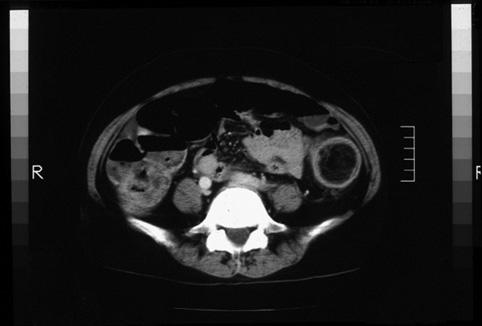

疾病(病理主体)的分类良性非上皮性肿瘤/脂肪瘤

部位(按器官分)大肠/降结肠

检查方法CT

肿瘤最大直径35~40